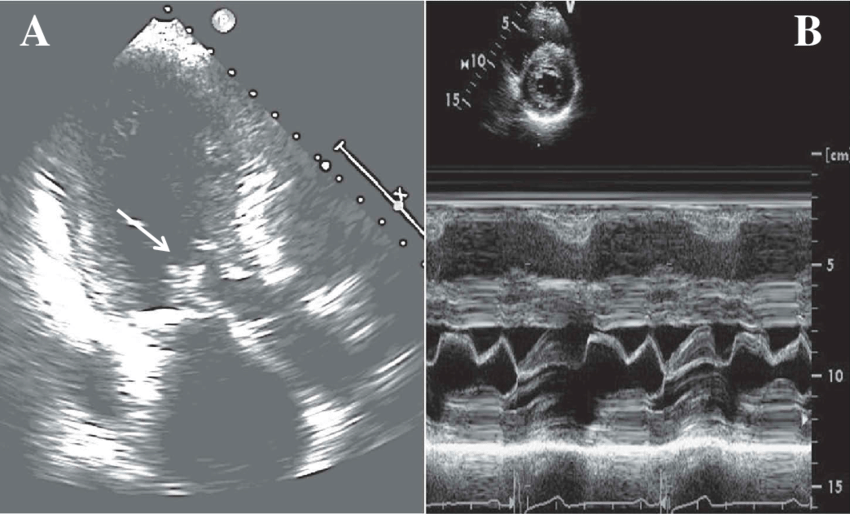

LV noncompaction CM

What is seen in this 2D image?